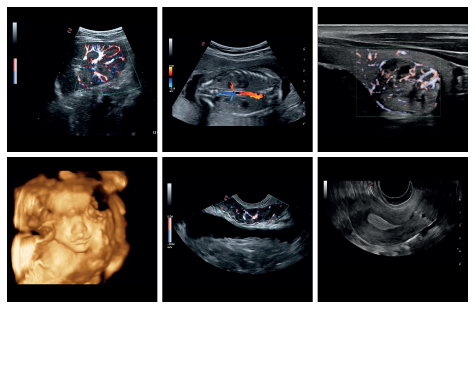

MyLab™Gamma incorpora imágenes de alta resolución y tecnologías avanzadas. Además, es compatible con una amplia gama de sondas, por lo que resulta una solución ideal para aplicaciones cardiovasculares, radiológicas, ginecológicas, musculo-esqueléticas y mucho más.